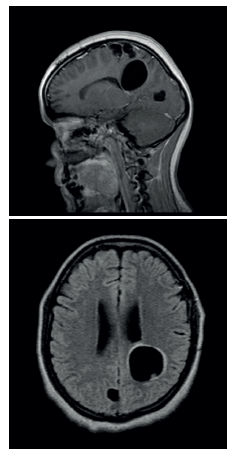

Cuatro meses después de la alta hospitalaria, la paciente refirió persistencia de cefalea, por lo cual se valoró en el servicio de consulta externa con RMN de control. En aquel estudio, se evidenció falta de respuesta de las lesiones descritas antes del manejo antiparasitario, con lesiones quísticas parietales con tendencia a la progresión (Figura 2). Por lo anterior, se planteó la posibilidad de estar frente a un caso de NCC resistente a manejo antihelmíntico o ineficacia propia del albendazol genérico, administrado durante el primer ciclo terapéutico.